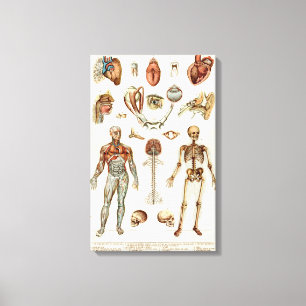

Vintage Illustration Human System Poster

PriceCA$52.05

Anatomy of The Human Body Canvas Print

PriceCA$185.00